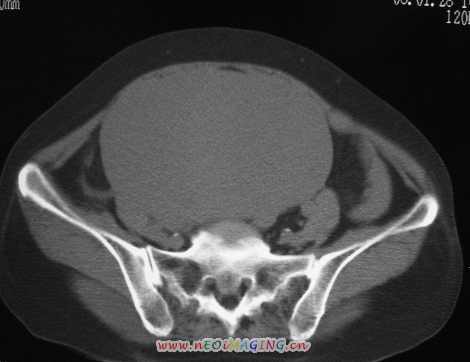

标题: CT11527:女56岁以右输尿管结石入院

女56岁以右输尿管结石入院

病灶位于下腹部盆腔,从子宫与膀胱明显受压后移看,应该来源于盆腹腔的占位,病灶实性部分密度均匀,左侧可见低密度灶,建议增强扫描,考虑:间叶性肿瘤,或硬纤维瘤,输尿管下段结石伴上段输尿管扩张

右侧盆腔占位,考虑来源于卵巢,囊腺瘤可能性大。

右侧输尿管结石。

1)盆腔占位性病变,考虑来源于卵巢,囊腺瘤可能性大。2)右侧输尿管第二狭窄处结石伴梗阻。

今天病人已经手术证实为右附件囊肿,右侧输尿管第二狭窄处结石伴梗阻!!!

[病理诊断] CT11527:右附件囊肿,右侧输尿管结石。